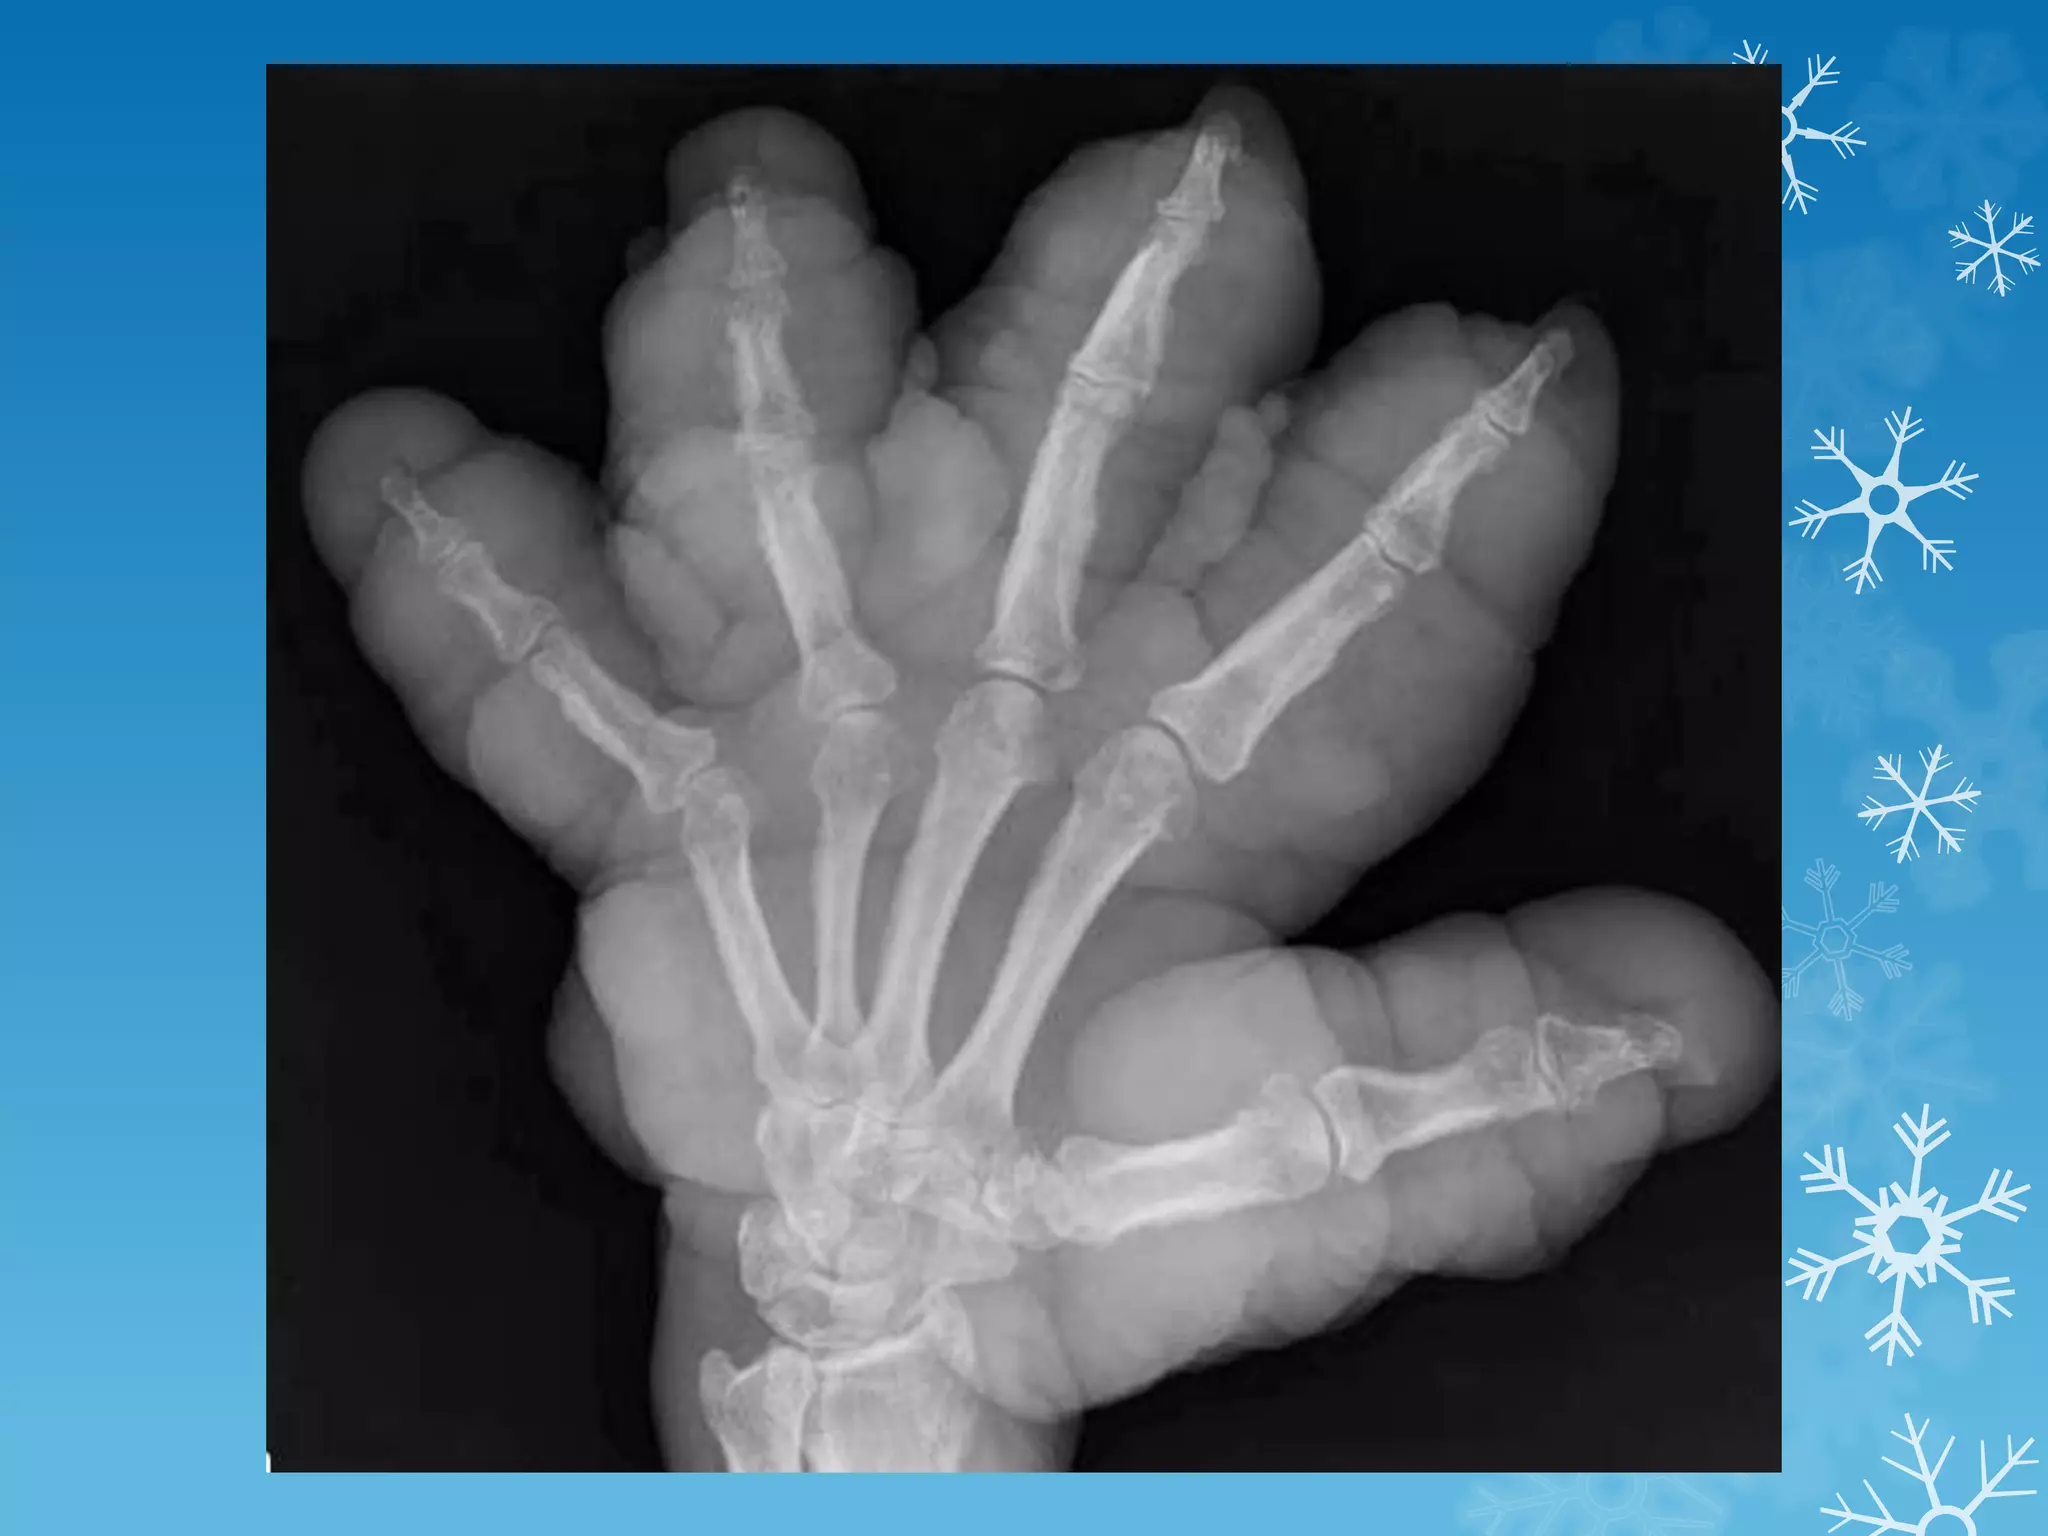

Anteroposterior view of the hand in this patient with sarcoid

demonstrates classic changes of bony involvement with this

granulomatous process.

Note the lacelike pattern of destruction, which is seen most

prominently in the proximal phalanges and in the distal third

phalanx.

Soft tissue swelling and some areas of severe bony dissolution

are also noted, which occur in more advanced patterns of

sarcoid.

These changes are typically limited to the hands but can rarely

occur in other parts of the skeleton.